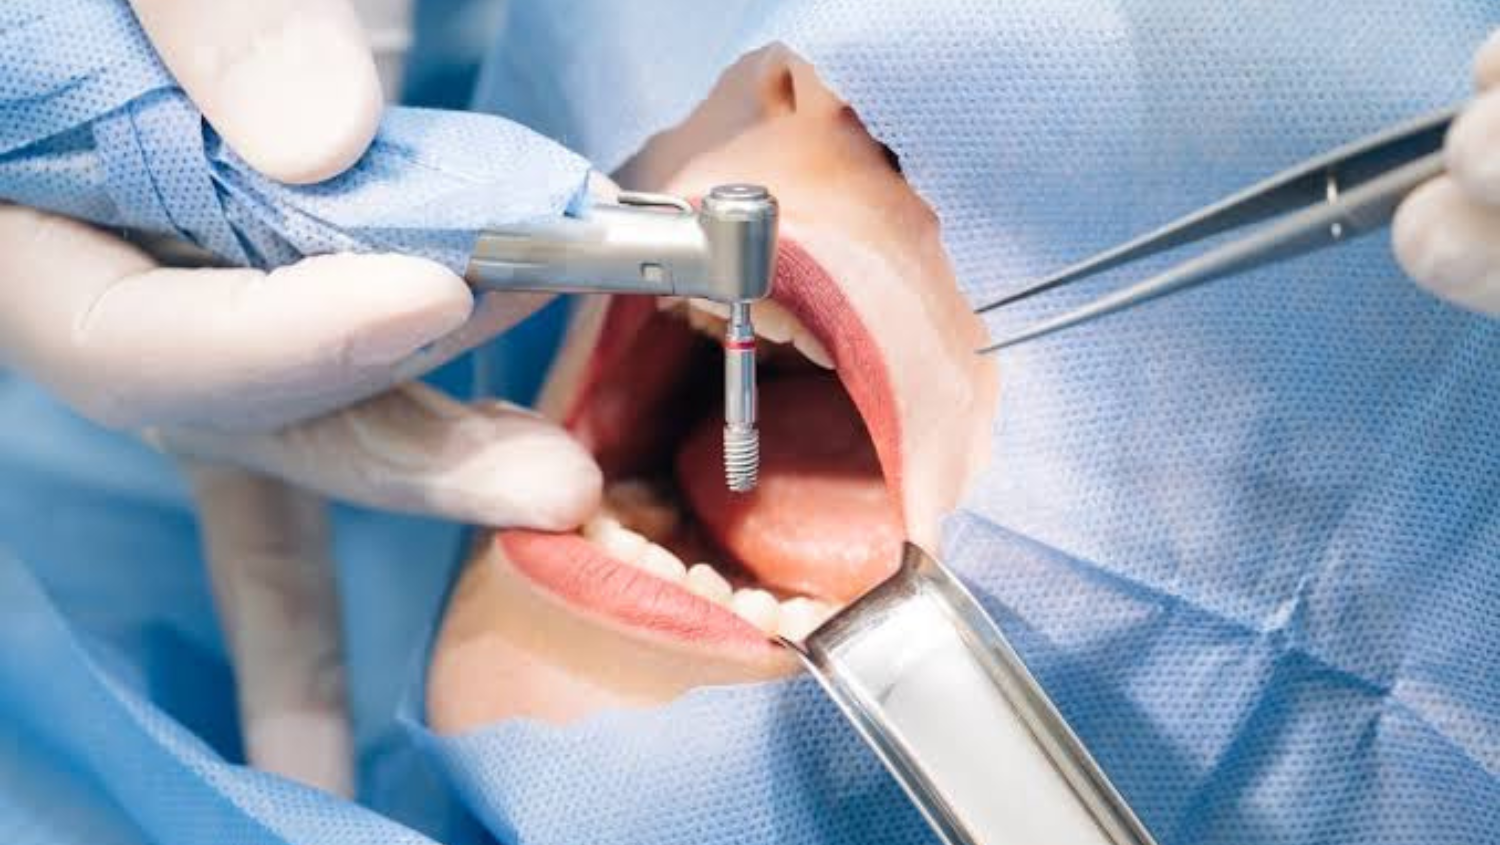

Fase Quirúrgica

Ya con una correcta planificación se procede a la fase quirúrgica, ésta según los resultados puede comprender una o dos intervenciones, la primera con el objetivo de preparar el hueso si fuera necesario y en la segunda insertar los implantes en el lugar elegido. En algunos casos es posible realizar ambas en el mismo acto quirúrgico.

Luego de esto será necesario esperar entre tres a seis meses para que los implantes se integren al hueso, y así podremos descubrirlos para realizar la conexión del pilar al implante mediante el tornillo de fijación.